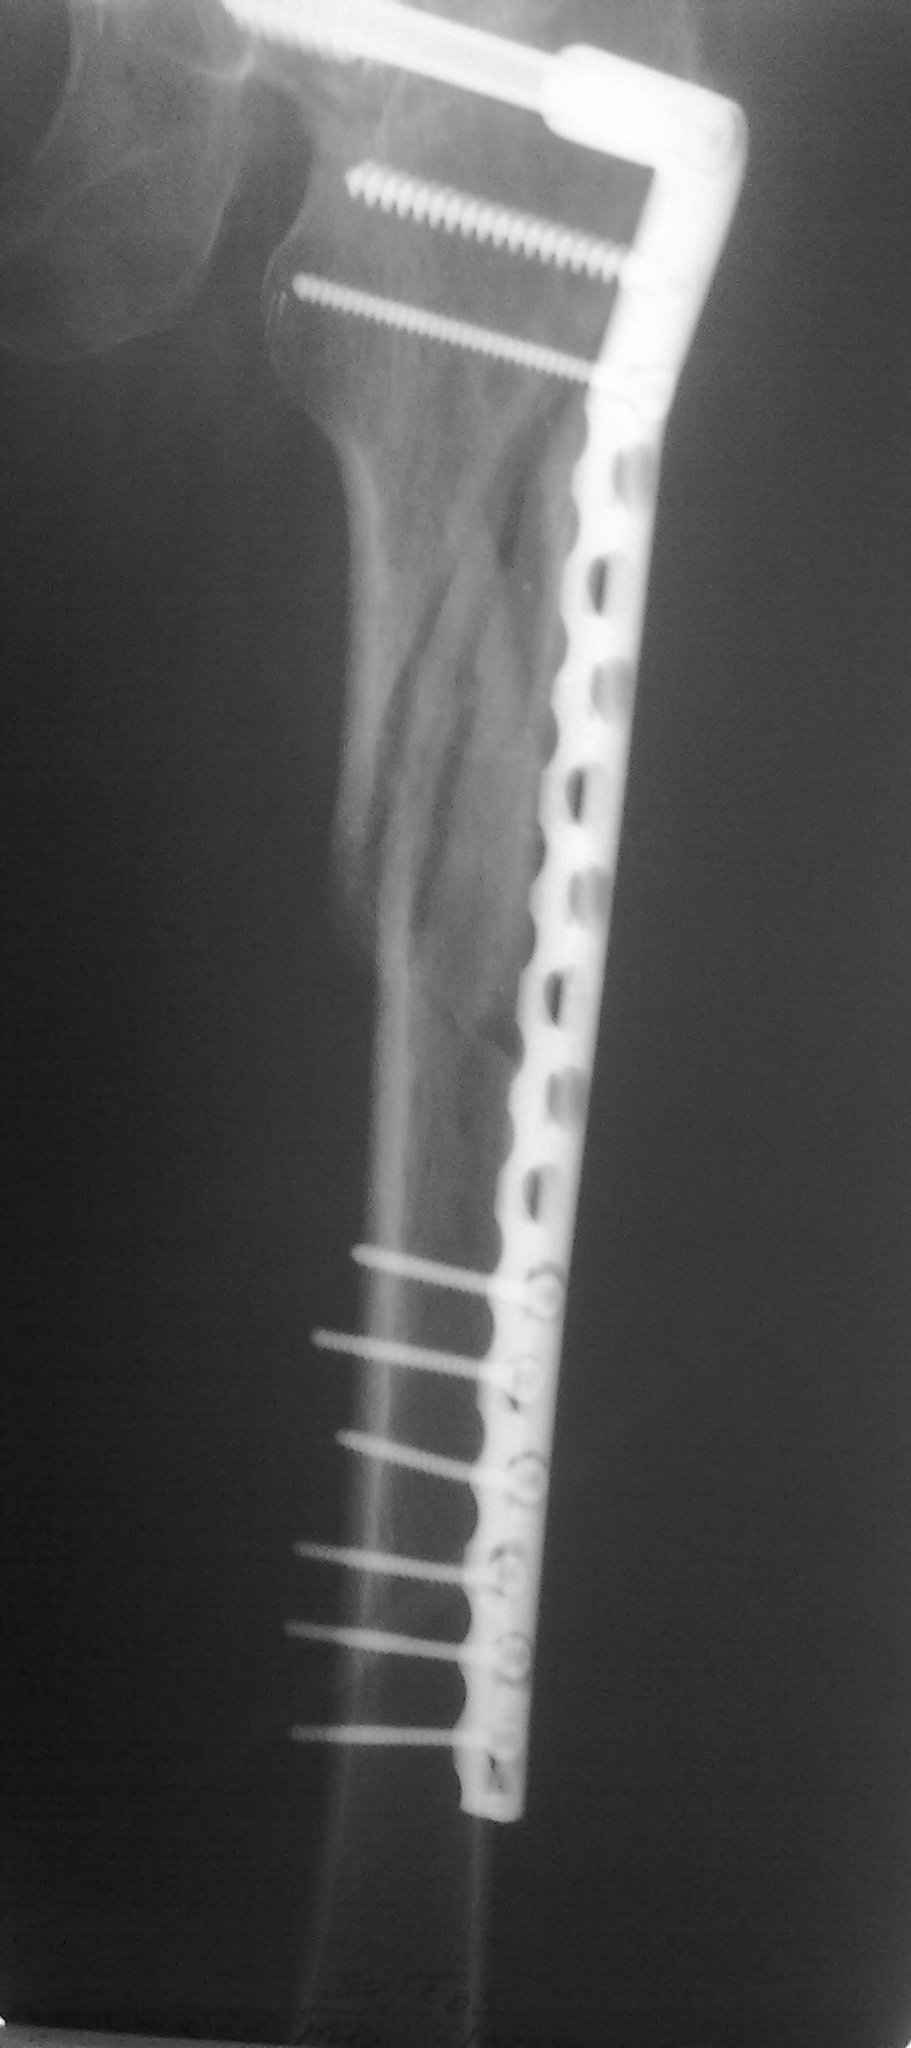

А может для первого опыта подобрать и перелом и больную полегче, а в данном случае ограничиться DCS?

День добрый! 240 мм однозначно короток, нужен миниум 300 мм, а то благие начинания заведут вас в ад осложнений. С диабетом на операции открывть ничего не нужно, только закрытая репозиция на ортопедическом столе под контролем ЭОПа. Без 100% анатомичной репозиции. Восстановить ось и ШДУ.

DHS, DCS , реконструкционный бедренный гвоздь всё это из другой оперы, не для этого перелома. Лучше потратьте время на поиски нужного удлиненного гамма-гвоздя и скорректируйте больную, чем не обдумано рисковать жизнью больной и своей репутацией (совестью).